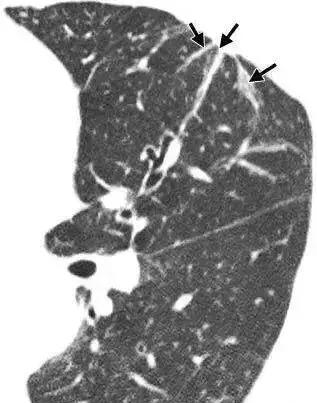

两肺索条、钙化,必要时定期复查

索条:指纤维性病变或纤维化,常见于慢性炎症或增殖性病变在修复愈合过程中,纤维成分逐渐代替细胞成分而形成瘢痕。说的再简单点就是“疤瘌”。

钙化:多属变质性病变,破坏的局部组织内钙盐沉积所致。说简单点就是各种原因导致的钙质在不该沉积的地方沉积了。

两者都属于陈旧性病变的范畴,要结合其它影像学征象和临床表现确定病因,建议1年复查一次。若医生考虑是结核病所致,一旦患者有临床症状应即刻复查;如果病变范围增大或钙化密度减低时,也要进一步检查。

Fig 2 肺内条索

Fig 3 肺内钙化